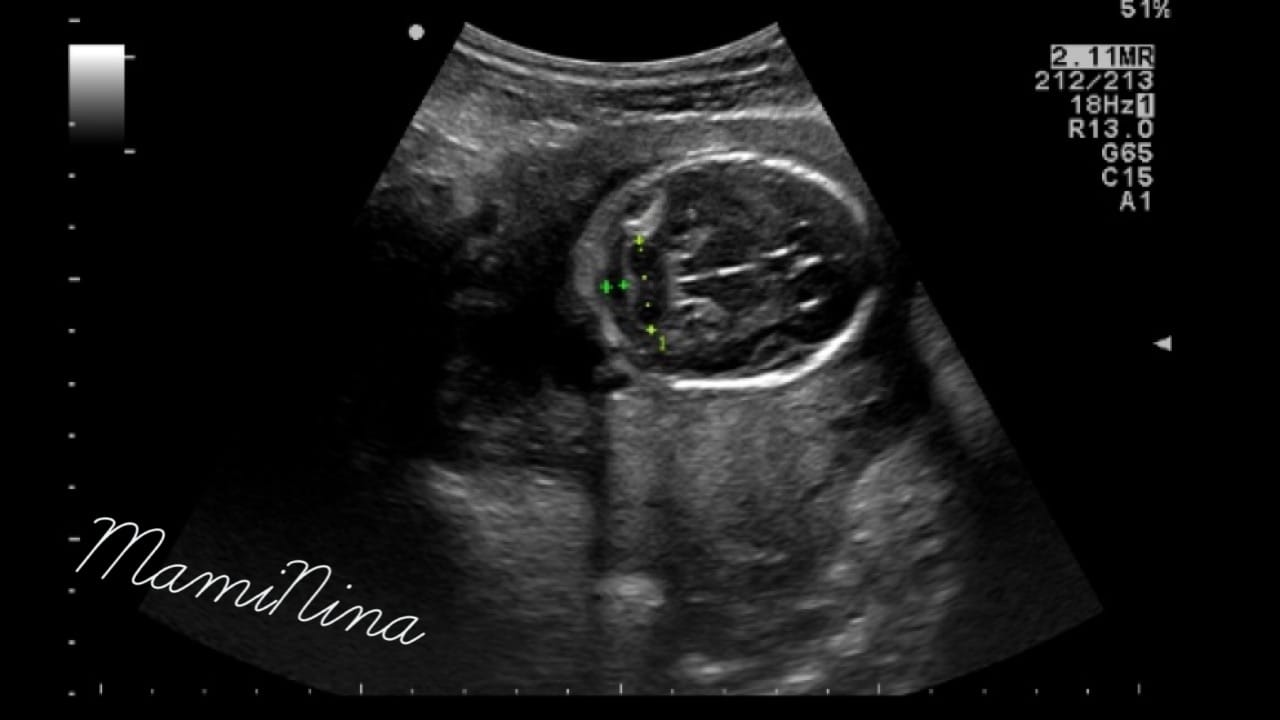

Zdravnica je izmerila dolžino maternice in pričela z ultrazvočnim pregledom. Za začetek z odličnim pogledom na utripajoči srček in njegove štiri prekate. Skozi pregled smo pregledali prav vse od začetka do konca, rokice, nogice, hrbtenico, rebra, usta, oči, res, ni da ni. Izredno se je potrudila in nama z možem pokazala vse, kar je le lahko. Pogledali smo tudi, kako je plod ravno v trenutku, ko smo opazovali profil obrazka nekaj prav na veliko pogoltnil, kar je bilo res prav zanimivo.

Med pregledom je bil seveda, tako kot vsak dan, v trebuščku pravi nogometni trening, zato smo tudi na ekranu videli, kako se premikajo roke in noge in kako je proti koncu pregleda začel plod svojo zadnjico tiščati ob trebušno steno. Vse skupaj res odlično čutim, saj se posteljica tokrat nahaja za gestacijsko vrečko, pri prvi sem vse skupaj čutila precej kasneje, ker je bila posteljica pred vrečko. Vodilni plodov del je zaenkrat glava in kar precej upam, da pri tem tudi ostane. Zaradi prvega poroda, ki se je končal s carskim rezom ravno zaradi medenične vstave, je tokrat, v primeru, da bo otrok spet sedel na ritki, skoraj sigurno edini možni porod zopet carski rez. Vseeno upam, da bom tokrat lahko dobila drugačno izkušnjo, katere me je, ne glede na izid, počasi že rahlo strah (priznam).

Glede na mere je trenutna teža ocenjena na 340 g, kar je popolnoma v mejah normale, s temi podatki pa se za nekaj dni premakne tudi predvideni datum poroda, ampak uradno v knjižici ostaja zapisan datum 2.7.2017 (prav noro lepe številke, ampak saj vemo, da se izredno malo otrok dejansko rodi na PDP).

(na dodanih slikah lahko vidite glavico, nogico in profil obrazka naše princeske)